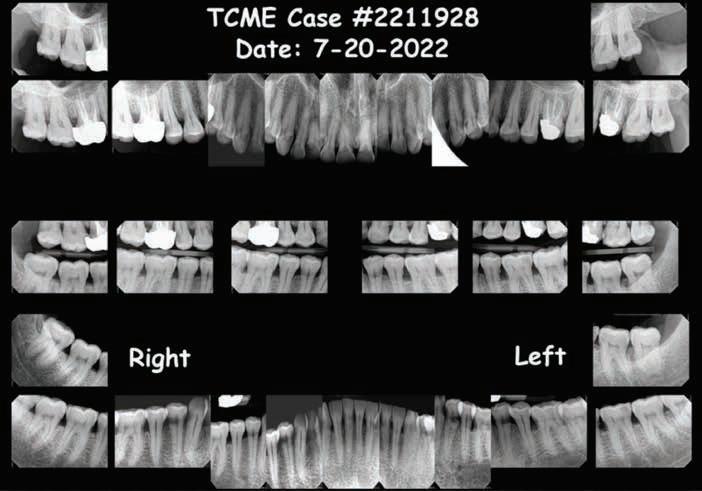

The Unidentified Individual: Tarrant County Medical Examiner (TCME) Case #2211928

Date of Death (Decedent found with lividity): June 28, 2022

Cause of Death: Hyperthermia

Manner of Death: Accident

Body Condition: Recent/Fresh

Sex: Male

Ancestry: Hispanic

Age: 40-60 years

Scene Description: An unidentified Hispanic male was found by a worker mowing grass near the back parking lot of a Domino’s restaurant in Ft. Worth, Texas, on 6-28-2022. The decedent was lying unresponsive in a supine position on the pavement between a dumpster and a cargo shipping container when Ft. Worth police arrived at the scene. Video surveillance obtained from the restaurant caught the decedent moving around on camera near the dumpster at 1800 hours on 6-28-2022. The decedent was clad in pants and a belt. No signs of medical intervention were observed, and brown emesis was present around the decedent’s mouth. No foul play was suspected.

Dental Evidence Recovered: Maxilla and Mandible

Right Left

Right Lateral View

Left Lateral View

Right Left Right Left

Periapical Tooth #3 (Root Canal Treatment)

Periapical Tooth #14 (Root Canal Treatment)

#3 #14

Dental

Closing

If you believe you have any dental records, dental radiographs, intraoral/extraoral dental photographs, dental scans, or other dental information regarding the unidentified Hispanic male decedent described above as TCME Case #2211928, please contact the Tarrant County Medical Examiner’s Office, phone (817) 920-5700, extension 8387, ask for Chief of Human Identification Services Christian Crowder, PhD, D-ABFA.